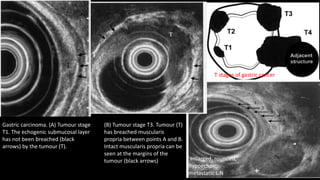

T stages of gastric cancer

enlarged, rounded,

hypoechoic,

metastatic L.N

Gastric carcinoma. (A) Tumour stage

T1. The echogenic submucosal layer

has not been breached (black

arrows) by the tumour (T).

(B) Tumour stage T3. Tumour (T)

has breached muscularis

propria between points A and B.

Intact muscularis propria can be

seen at the margins of the

tumour (black arrows)